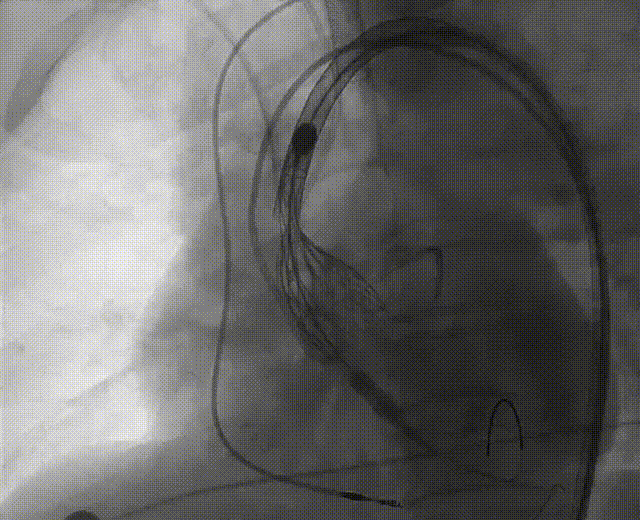

根部造影

左冠脉提前植入延长导管,预埋冠脉导丝。

20mm球囊预扩张,无腰征,无造影剂泄露。

vitaflow tav24瓣膜轻松过弓初始定位瓣环0位开始释放,班第一次释放瓣膜在转移到瓣上,综合决定回收采取第二次瓣膜释放。

第二次精准零位释放,决定完全释放。

释放后多体位观察造影,瓣膜位置良好,展开良好,轻微瓣周漏。